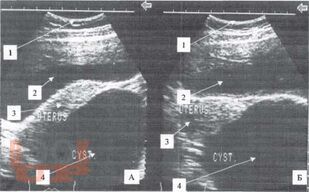

Диагностика и лечение опухолей и опухолевидных образований яичников у девочек и подростков является актуальной проблемой. Совершенство методов диагностики при данной патологии, хорошо зарекомендовавших себя во многих областях медицины, способствует внедрению их в клинику детской гинекологии, онкогематологии, детской хирургии.

Разнообразие средств диагностики, отличающихся по физическим данным и разрешающим способностям, а также по стоимости аппаратуры и самих исследований, часто ставит врача перед сложной проблемой определения необходимого минимума применяемых методов, последовательностью их выполнения и интегрирования результатов разных исследований в единую диагностическую концепцию.